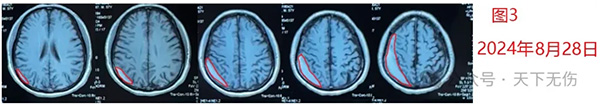

2024年7月15日,他在一位北京著名神经外科教授推荐下从南方来找我,多年的经验告诉我,他的头晕应该就是这个残余血肿引起。然后给予他汀加激素加头颈淋巴按摩疗法,治疗1周出院时复查即已经见到血肿缩小,但头晕减轻并不明显。也因此他仍然忧心忡忡,问我自己到底能否治愈?我反复安慰他,一定会治愈。在接下来漫长的等待药物发挥作用时间中,他间断联系我,说脸上起疹子了,体重增加了,头晕减轻,却仍然没有消失。我感知到他的忧郁,鼓励他,血肿变得越来越小,症状越来越轻,而这些副作用是我们预知的药物副作用,一定会随着停药而完全消失,他的信心逐步增强。9月23日,他突然主动联系我告诉我好消息,说当地医生复查时已经告诉他,他的血肿完全消失了(图2),他的头晕症状也完全消失了。

图2

他热情邀请我到他所在城市过国庆节,一定要好好招待我。我因为忙碌,肯定爽约。但年轻患者的治愈还是让我颇感欣慰,年轻的慢性硬膜下血肿患者是最容易焦虑的一个群体。

从这例患者治疗经过我体验到,我不能预知他的手术有没有必要,但是我可以预知,如果术前就他遇到我,我会告知他这个疾病还有其他的治疗方法。至于头晕的症状是由残余血肿引起还是耳石症引起,确实和个人诊疗的经验有关。因为耳石症罕见发生于年轻人,并且针对性治疗无效,他又有明确的未治愈血肿,因此我判断还是残余血肿导致了患者的临床症状,事实也证实了这一点。